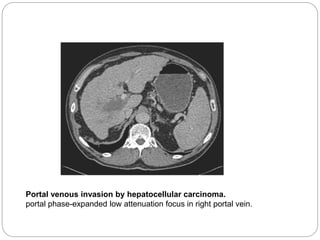

Portal venous invasion by hepatocellular carcinoma.

portal phase-expanded low attenuation focus in right portal vein.

Portal venous invasionby hepatocellular carcinoma. portal phase-expanded low attenuation focus in right portal vein.